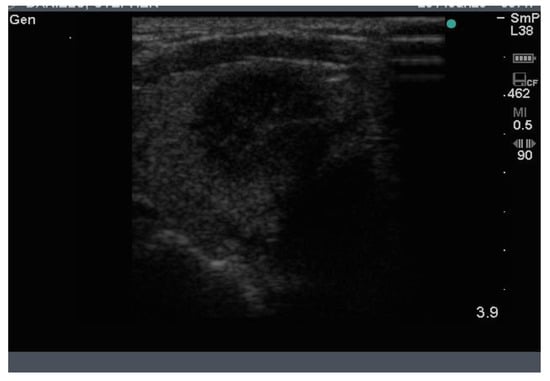

4. Follicular Nodules

Follicular nodules are much less common than colloid nodules with a different appearance on ultrasound; they are more cellular, giving a solid appearance, with a whitish colour, i.e., less hypoechoic. They too have a sharp edge and halo and grow slowly over time []. The problem with these lesions is that FNAB is unable to differentiate between a benign follicular adenoma and follicular cancer, and if the latter is suspected, thyroid surgery is the final arbitrator. About 10% of benign thyroid nodules are follicular, and most of them end up being removed. Two examples of follicular nodules that were finally proven to be benign are shown in Figure 4. On follow-up ultrasound (US), 6–12 months later, repeat biopsy might be indicated if a nodule has grown by 20% or more in two or more dimensions; benign nodules also grow, but less quickly.

Figure 4.

Two examples of follicular nodules that were shown at surgery to be benign. The nodules are roughly oval shaped, slightly hyper echoic and have sharp edges and, particularly, the bigger of the two, thick halos.